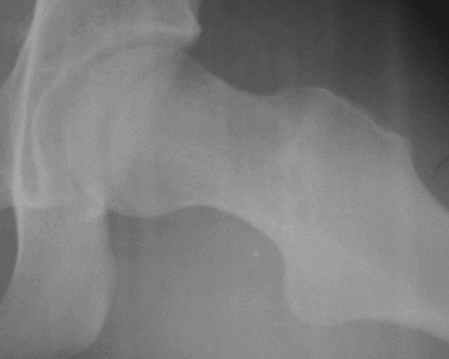

Уважаемые коллеги! Заканчивая обследование больного с переломо-вывихом бедра сделал ему обычные R-томограммы. Кажется удалось "поймать" и отломок и донорское место. Мои выводы - в скиаграмме. Считаю, что это передне-нижний фрагмент головки, образовавшийся вследствии отрывного перелома. На томограммах отломок обозначаю длинной стрелкой, а место откуда он оторвался - более короткой. Учитывая тот факт, что его размеры по КТ 25 х 15 мм считаю, что его фиксация на место необходима для профилактики артроза, что при 16-ти летнем возрасте пациента важно в плане максимального отодвигания эндопротезирования. Планирую оперировать его 24.05.05 г. Результаты представлю.

Прямой при поступлении

Несколько соображений к "картинкам". На прямом снимке и КТ-томограммах все типичные линии вертлужной впадины: крыша, передняя стенка, задняя стенка - сохранены. На КТ-сканах 6 и 7 появляется фрагментация головки. С учетом R-томограмм отломок расположен спереди-снизу, а не сзади-сверху от сустава, как написано в описании КТ.